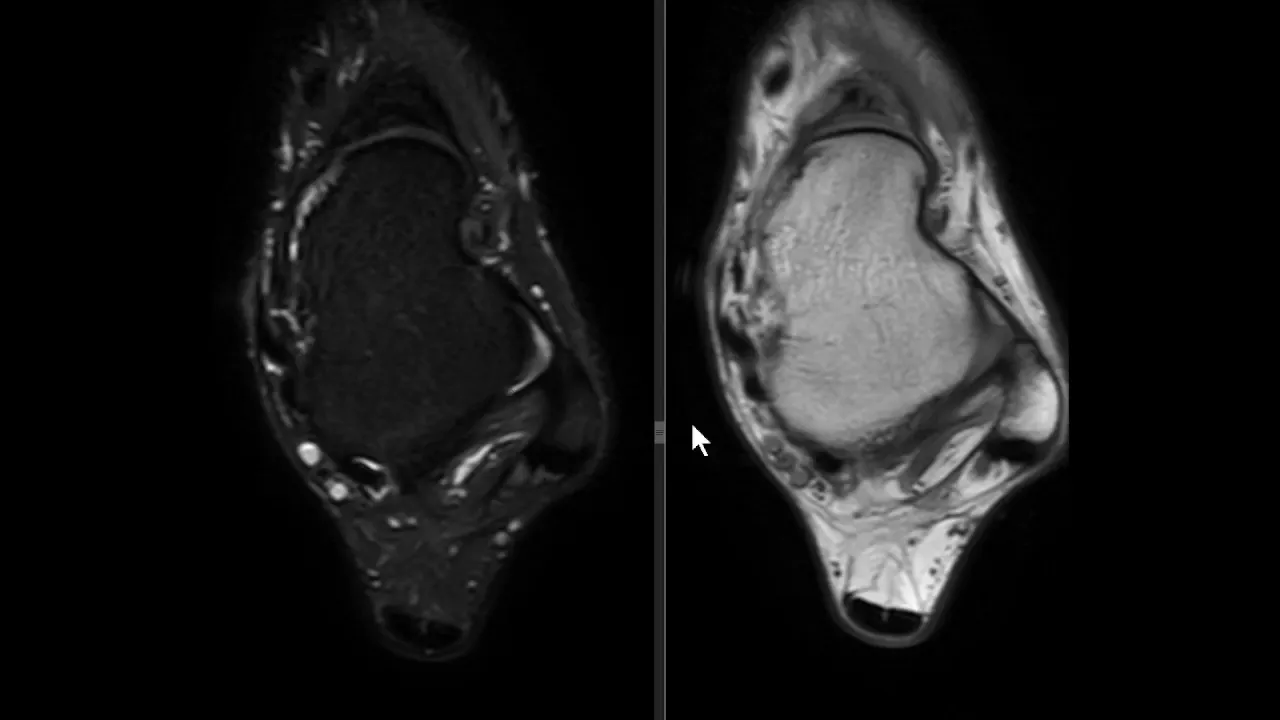

saudações vamos aqui a Mais Um Caso o contexto clínico é de um paciente que sofreu uma torção aguda do tornozelo e temos essa ressonância magnética aqui um axial DP com saturação de gordura e vamos observar aqui aqui é a fíbula corte aqui no plano axial aqui a fíbula aqui o talos aqui a tíbia né então o ligamento tíbio talar anter inferior está íntegro vamos descendo aqui aqui é a topografia do ligamento talofibular anterior aqui o ligamento talofibular posterior e você observa aqui no ligamento talo fibular anterior veja que ele está espessado está com hipersinal e

você nota nitidamente uma solução de continuidade né uma ruptura aí do ligamento talofibular anterior e edema ao seu redor existem outras alterações mas a gente vai se ater a essa alteração o ligamento talofibular posterior ele tem esse aspecto radiado né rajado é normal e o ligamento calcâneo fibular esse aqui na ponta da seta está íntegro apesar de haver edema ao redor dele então o ligamento talo fibular anterior rompeu e essa é a rotura mais frequente ligamentar no tornozelo do ligamento talofibular anterior aqui pra gente ver um comparativo com um tornozelo normal você Observe aqui a

fíbula aqui o talos e aqui você vê o ligamento talo fibular anterior aqui é uma sequência T1 e aqui uma sequência T2 com saturação de gordura você veja aí o ligamento talofibular anterior veja como ele é né em condições normais aí o ligamento talofibular anterior aqui o talo fibular posterior n talo fibular posterior ele tem esse aspecto rajado e descendo um pouco mais o calcâneo fibular fininho aqui subindo calcando fibular saio daqui e vem para cá mas o importante aqui É vermos o ligamento talo fibular anterior normal o aspecto normal dele ok Neste vídeo era